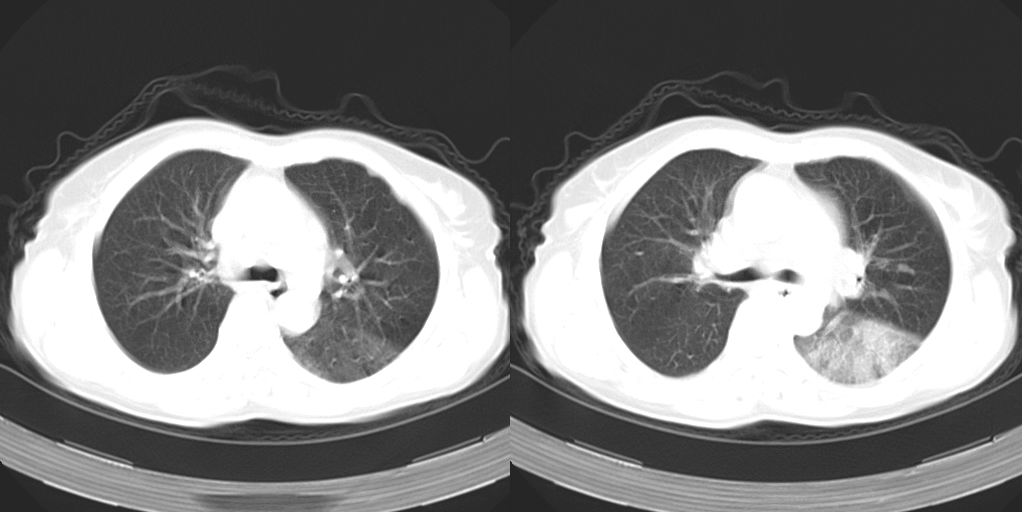

以下是引用dyqct在2007-1-23 15:01:00的发言:[br]左肺下叶实变、略萎陷,近肺门下部密度不均。上腔静脉后及隆突前见肿大淋巴结。余未见异常。[br]考虑:1、左肺下叶中心型肺癌伴肺不张、纵隔淋巴结转移;[br] 2、建议增强扫描并做任意平面重建确定肿块范围及支气管受累情况。

以下是引用同在2007-1-23 19:59:00的发言:[br]左肺下叶中央型肺癌伴肺不张及纵隔淋巴结转移.